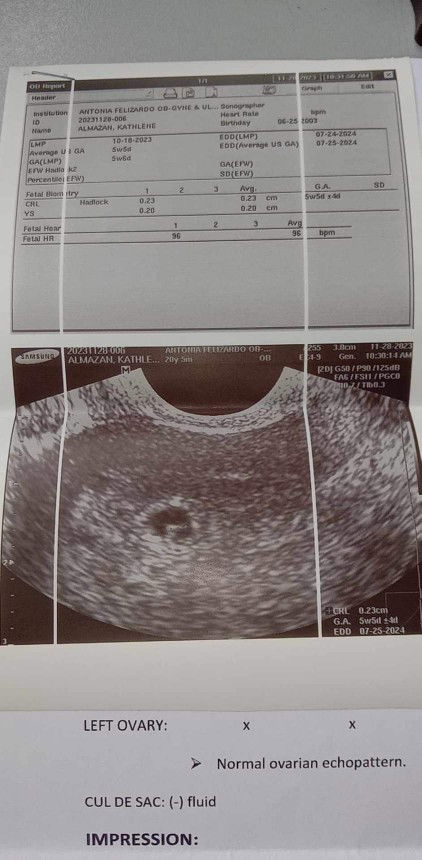

Threatened miscarriage. What to do? Transvaginal ultrasound may bleeding pero may heart beat si baby

So to make the story detailed. I had my first checkup this day since may nakita akong light pink spotting yesterday and today bago ako pumasok sa clinic nagkaron ako ng red na spotting na. So as you can see ito yung result nung transvaginal ultrasound ko. May bleeding pero may heart beat na si baby. Niresetahan ako ng duphaston as well as yung isa pa, and yung folic acid. How many days ba ang tinatagal ng pagdudugo if ever nagstart na ako uminom ng gamot today.